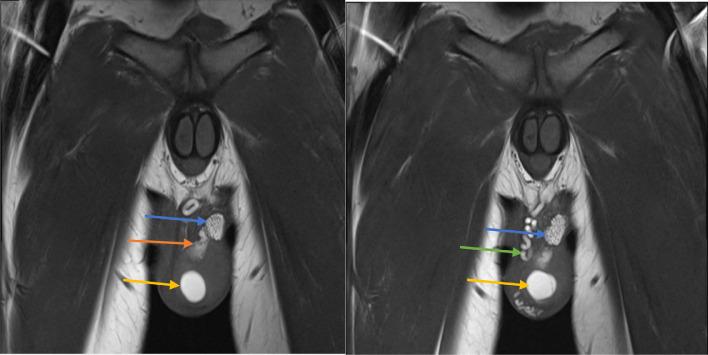

Zinner syndrome comprises a triad of unilateral renal agenesis, ipsilateral seminal vesicle cyst, and ejaculatory duct obstruction, which can be accompanied by additional abnormalities of the genitourinary tract in some cases. Patients may be asymptomatic or present with urinary, reproductive, and/or local pain symptoms. Diagnosis is most commonly achieved via MRI. Here, we present the case of an 18-year-old male previously diagnosed with unilateral renal agenesis, who presented with testicular and penile pain, along with urinary urgency and frequency. MRI of the abdomen and pelvis revealed all three components of Zinner syndrome as well as an ectopic ureter emptying into the seminal vesicle. Our case adds to the existing limited literature on this rare syndrome and broadens the understanding of how this syndrome can present both clinically and radiologically.

齐纳综合征包括单侧肾缺如、同侧精囊囊肿和射精管梗阻三联征,某些情况下可伴有泌尿生殖道的其他异常。患者可能无症状,或出现泌尿系统、生殖系统和/或局部疼痛症状。诊断最常用的方法是磁共振成像(MRI)。在此,我们报告一例18岁男性病例,该患者此前被诊断为单侧肾缺如,现出现睾丸和阴茎疼痛,伴有尿急和尿频。腹部和盆腔的MRI显示了齐纳综合征的所有三个组成部分,以及一条异位输尿管排入精囊。我们的病例补充了关于这种罕见综合征的现有有限文献,并拓宽了对该综合征在临床和影像学上表现的认识。